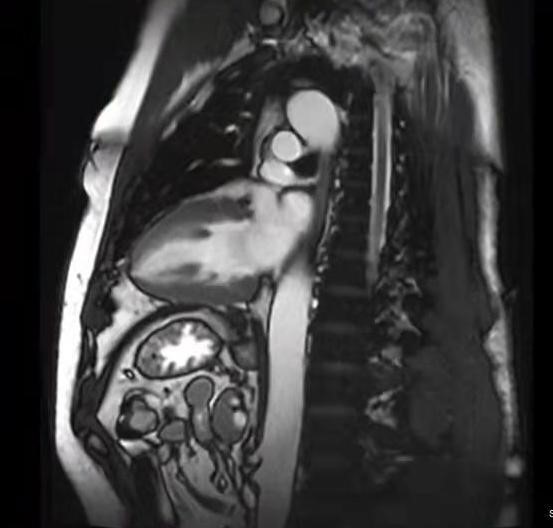

心脏MRI图像示例:

图1. 左室垂直长轴,主要显示左心室,左心房,二尖瓣等解剖结构

图2. 左室水平长轴四腔位,主要是显示心脏四个心腔以及室间隔、房间隔、二尖瓣、三尖瓣、乳头肌等结构。